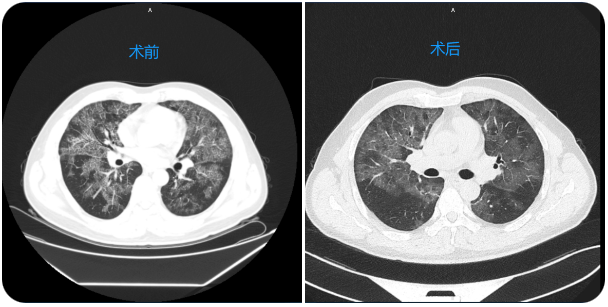

治疗前后对比